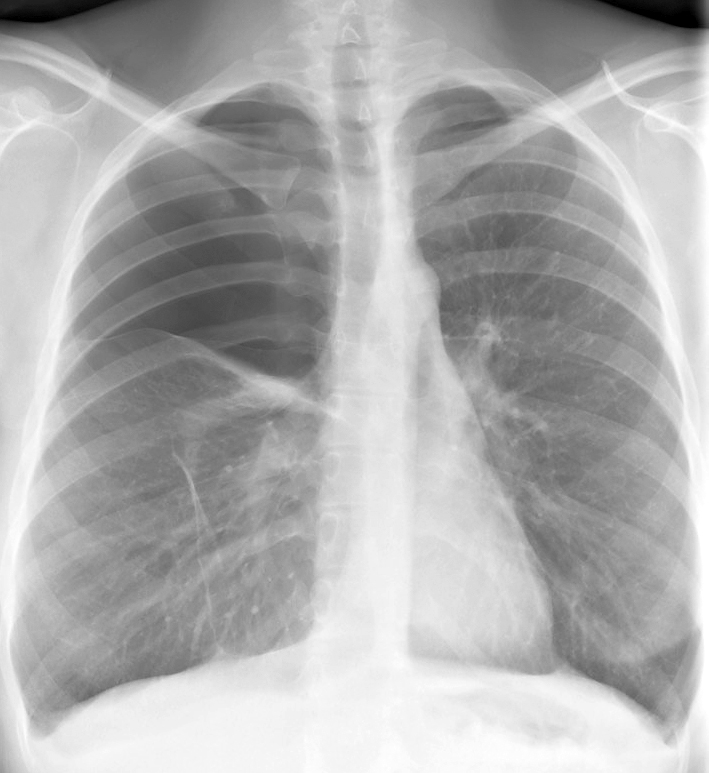

Gallery COPD bulla RUL

bulla RUL